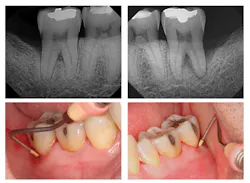

Figure 1: Pre-treatment radiographs

The patient was 45 years old with at least one known family member having periodontitis. He had a normal level of C-reactive protein (2.0 mg/L), slight elevation of blood pressure (146/87 mmHg), low-density lipoproteins (130 mg/dL), and slight deficiencies of vitamin D and thyroxin. He used an appliance to control bruxism and had a history of orthodontic treatment, although malocclusion was still present. A periodontist had recommended extraction of teeth Nos. 18 and 31, which had vertical defects on the distal surfaces (see Figure 1). On both teeth, recession was less than 1 mm on all surfaces, and pocket depths were at least 7 mm on the buccal and distal surfaces. Tooth No. 18 had 11.8 mm bone loss on the distal surface, a Class II buccal furcation with a 10 mm pocket, and a Class I lingual furcation with a 5 mm pocket. Tooth No. 31 had 8.4 mm bone loss on the distal surface and a Class II furcation with an 8 mm pocket on the buccal surface (see Table 1).